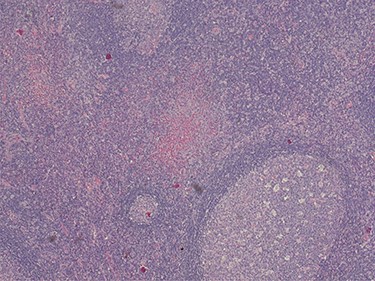

Because of the recent increase in the size of the swelling, the patient presented to our clinic and agreed to undergo excision of the swelling. A well-circumscribed swelling measuring 2.5 cm × 1.5 cm which was soft to firm in consistency was completely excised (Fig. 1). Histopathological examination showed sections of lymph node with florid follicular and germinal center hyperplasia (Fig. 2), and paracortical expansion by plasma cells, small lymphocytes and mast cells (Fig. 3). Marked eosinophilic infiltration with focal micro-abscess formation was present (Fig. 4). The features were consistent with Kimura’s disease. There was no evidence of malignancy. At 6 months follow-up, the patient had no evidence of recurrence.

Histopathology of the lymph node showing paracortical expansion by plasma cells, small lymphocytes and mast cells, and areas containing eosinophilic micro-abscesses (accumulation of inter-follicular eosinophils). Haematoxylin and Eosin stain. Magnification ×5.